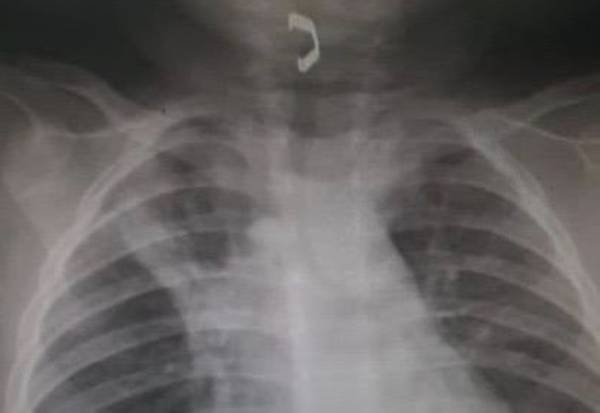

تمكّن فريق طبي متخصص بمدينة الملك سعود الطبية، من إنقاذ طفل يبلغ من العمر سنة وستة أشهر، وذلك بعد دخول جسم معدني إلى مجرى الهواء، وتعرض حالته للخطر. وأوضحت المدينة أن الطفل استقبلته طوارئ الأطفال بالمدينة عن طريق تحويل من أحد مستشفيات محافظة المجمعة، وعند وصول المريض إلى طوارئ مستشفى الأطفال، تم نقله إلى العمليات بشكل عاجل، وتم عمل منظار للقصبة الهوائية، وفتح مجرى الهواء وإزالة الجسم الغريب الذي كان يعوق مجرى التنفس. وأكدت المدينة أن الطفل بحالة صحية جيدة، ويستعد للخروج من المستشفى خلال الأيام القليلة القادمة. يذكر أن العملية أجريت بقيادة استشاري ورئيس قسم جراحة الصدر الدكتور محمد العمصي، وبالتنسيق مع طوارئ مستشفى الأطفال، وأطباء التخدير، وأطباء الأنف والأذن والحنجرة.